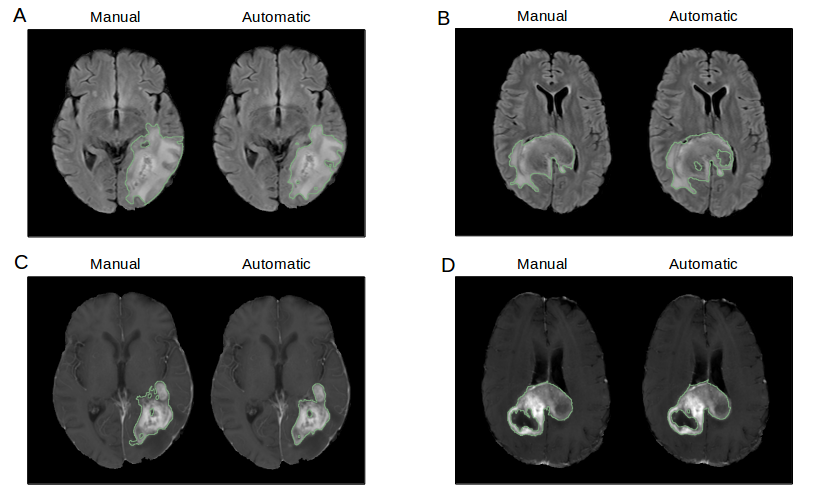

Pathological volume monitoring, and thus pathological tissue segmentation, is essential for assessment of treatment response and prognosis in glioblastoma treatment. [40, 41] Furthermore, volumes and imaging features derived from delineated tumor regions can be used for downstream prediction of molecular biomarkers, treatment response, progression, and survival.[42, 43, 44, 45]. Unfortunately, manual delineation of tumor boundaries can be challenging and subject to inter- and intra-rater variability, resulting in low reproducibility even among expert radiologists and oncologists. Additionally, it is a laborious task especially for high-resolution scans which can have numerous image slices. This diverts clinicians’ time away from other clinical and research tasks, as well as other patients. There are two tumor regions that are of key interest to the clinician. The first is the whole tumor, which consists of edematous tissue, non-enhancing, enhancing tumor, and necrosis. This is best seen on the T2 FLAIR sequence and represents the total tumor burden. The second is contrast-enhancing tumor, which represents regions of breakdown of the blood brain barrier. [46]

The Glioblastoma Segmentation module uses two 3D U-Net architectures. The first creates a binary labelmap of a region-of-interest defined as whole tumor. The output of this network is fed as an additional channel into a second network, which predicts a binary labelmap of enhancing tumor alone (Figure 6). Both networks take in 32x32x32mm patches extracted from FLAIR, pre-contrast T1, and post-contrast T1 patient MR sequences, stacked channel-wise.

Both U-Nets have a depth of four max-pooling layers, with two convolutional layers between each pooling layer, leading to a U-Net architecture with 18 convolutional layers. The network is trained on the BRATS 2017 dataset as well as a clinical trial patient cohort from the Massachusetts General Hospital [11, 12, 47, 48].